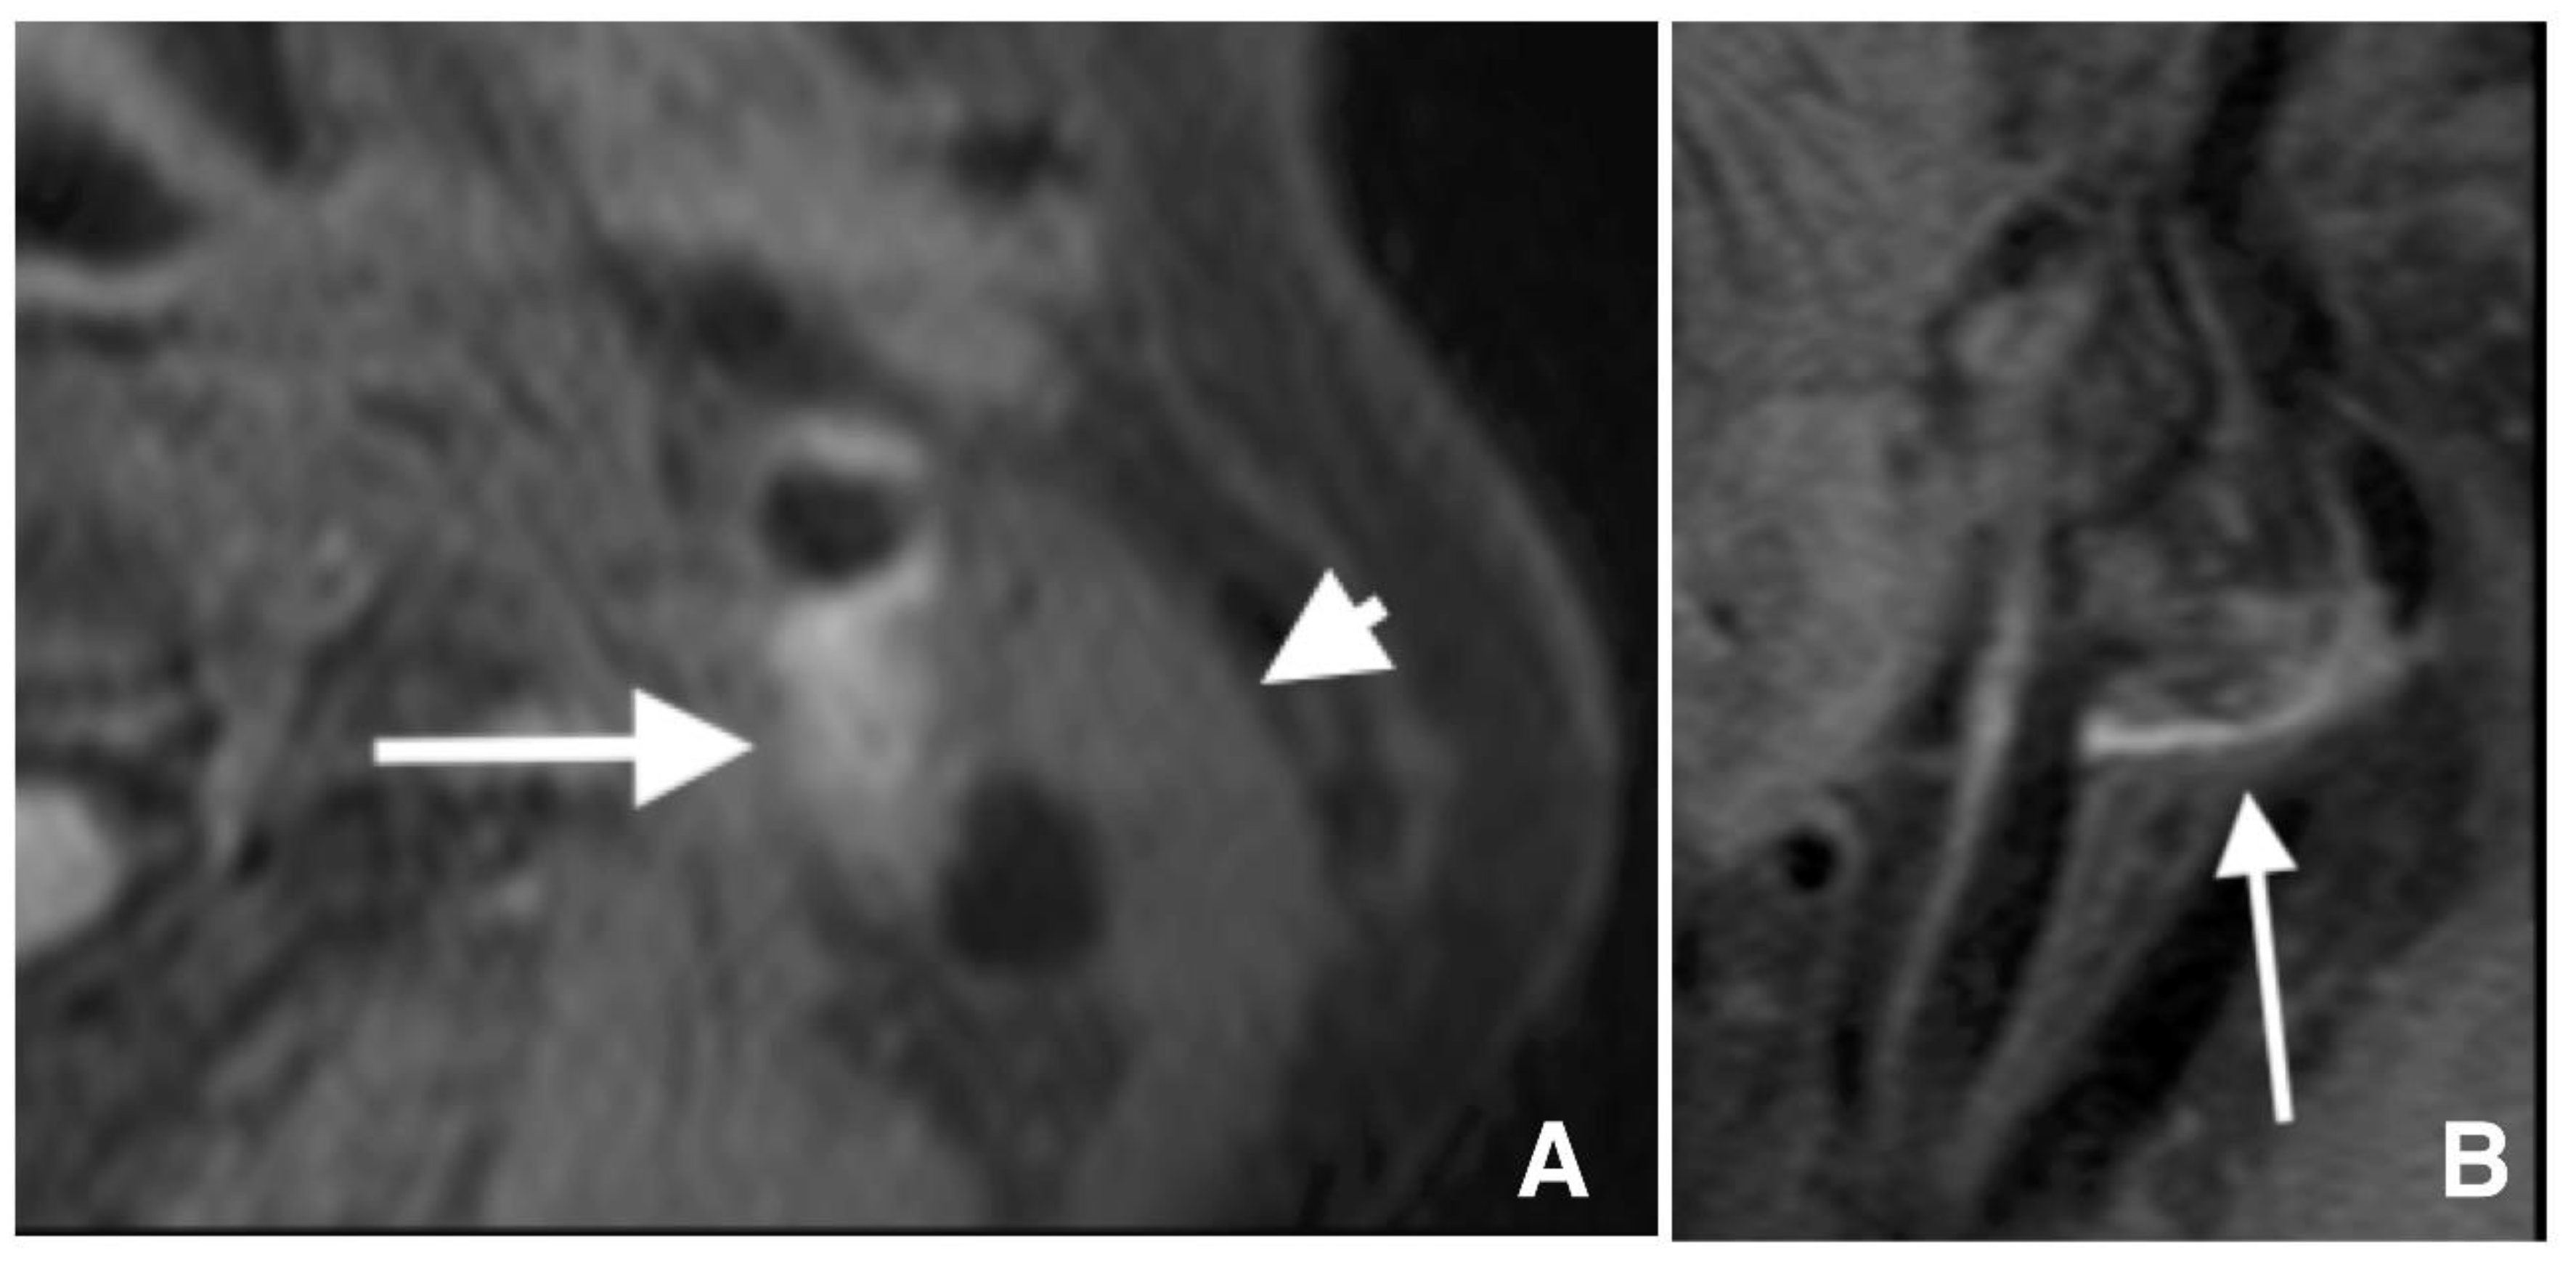

The plaque and proximal sternocleidomastoid muscle signal intensities were measured on axial FS 3D T1WBB MRI at a workstation (Zioworkstation2, Ziosoft, Inc., Tokyo, Japan). Lesions with IPH were defined as lesions showing hyperintensity on FS 3D T1WBB MRI, and hyperintensity was defined as an rSI ≥ 1.40 (Figure 2). The plaque rSI was calculated using the following formula: (plaque SI)/(sternocleidomastoid muscle SI) [10].

Figure 2.

T1-weighted black blood magnetic resonance imaging reveals a high signal intensity of 1533 in carotid lesions (arrows) and a signal intensity of 636 in the sternocleidomastoid muscle (arrowhead) in axial (A) and sagittal (B) images, indicating a relative signal intensity of 2.44.